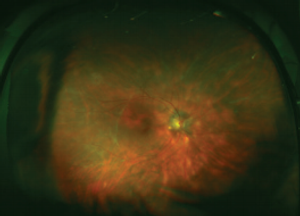

Meeting the challenge of noninfectious uveitis

Tackling the challenge of noninfectious uveitis

Chronic cases can be difficult for retinal specialists, but treatment is satisfying.